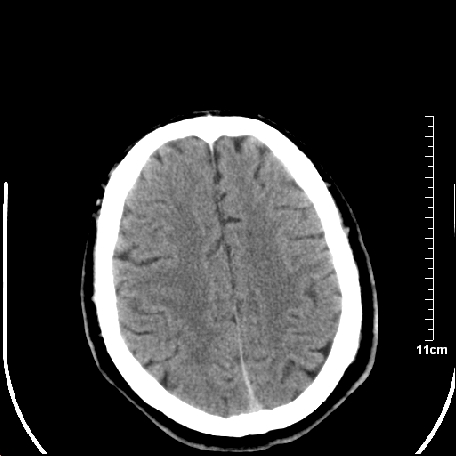

外伤患者,什么病,

外伤患者,没什么症状,

双侧外侧裂,左侧脑沟见高密度结节影,边清,还有鞍上池层面密度也高

都是血管。

脑血管硬化?高血红蛋白症?

高血红蛋白症可能

高血红蛋白症

高血红蛋白血征

1.左额叶脑软化灶。

2.老年脑,基底动脉硬化迂曲。

基底动脉硬化迂曲。高血红蛋白血症。